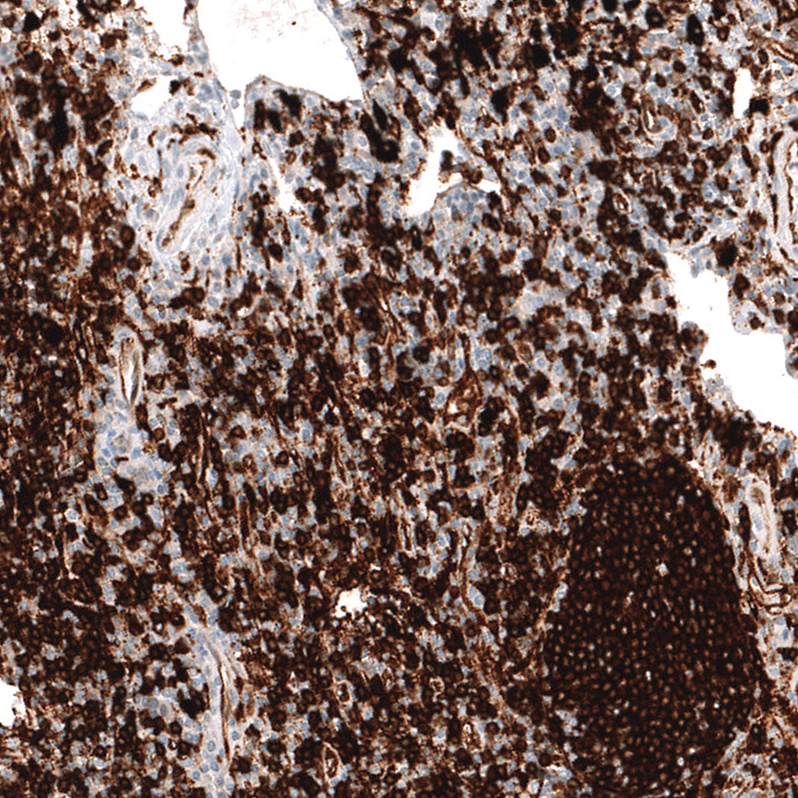

Immunohistochemistry analysis in human lymph node and testis tissues using AMAb91674 antibody. Corresponding HLA-DRA RNA-seq data are presented for the same tissues.